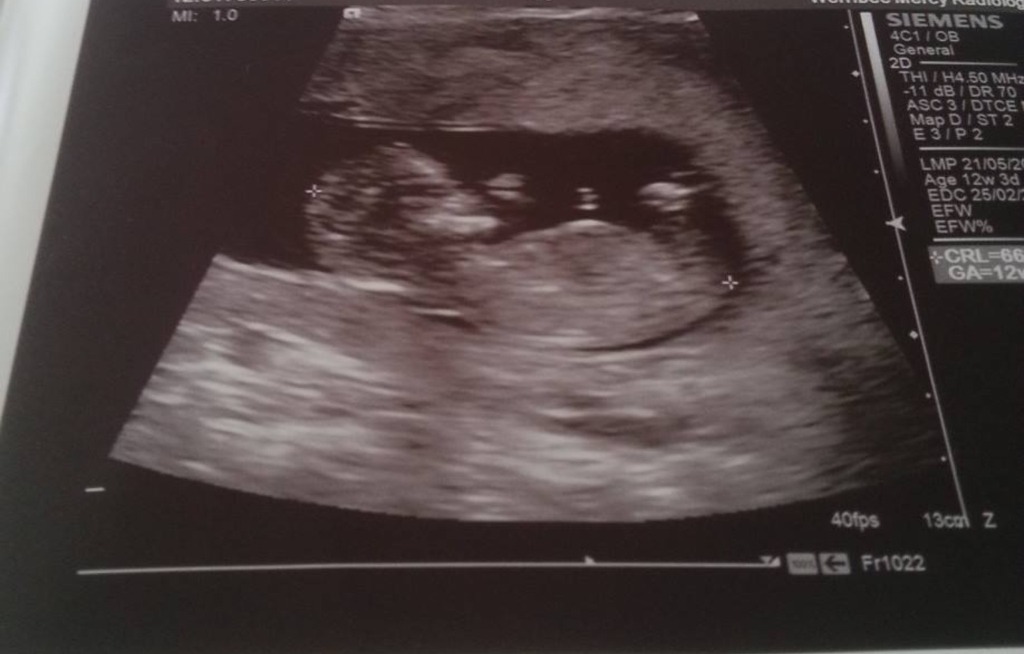

This is a friends scan and she is desperate to know if anyone can see a nub. After two boys she would love a girl.

Sorry, I can't see the nub.